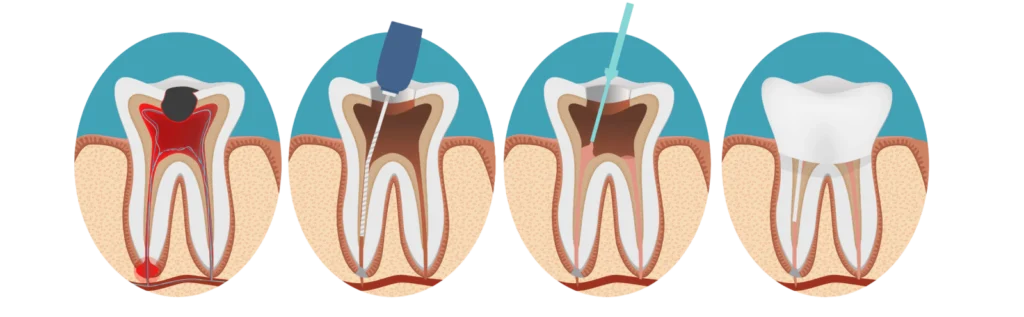

Déroulement du traitement de canal

Le traitement de canal, ou dévitalisation, consiste à retirer la pulpe infectée, à nettoyer les canaux de la dent, puis à les remplir pour éviter toute nouvelle infection.

3. Accès à la pulpe

Une fois l’anesthésie appliquée, la dent est ouverte pour permettre l’accès à la pulpe dentaire. Le dentiste retire la pulpe infectée ou morte, ce qui permet d’éliminer la source de l’infection.

4. Désinfection et nettoyage

Les canaux radiculaires sont soigneusement nettoyés et désinfectés pour éliminer les bactéries et autres résidus. Ce nettoyage en profondeur est essentiel pour prévenir toute réinfection future.

5. Remplissage des canaux

Une fois que les canaux sont nettoyés, le docteur les remplit avec un matériau de scellement appelé gutta-percha. Ce matériau permet de sceller les canaux et d’éviter que des bactéries ne se développent à nouveau à l’intérieur.

6. Restauration de la dent

Le dentiste restaure la dent en la scellant avec une obturation permanente. Dans certains cas, une couronne est posée sur la dent pour renforcer sa structure et garantir sa durabilité et son apparence esthétique.